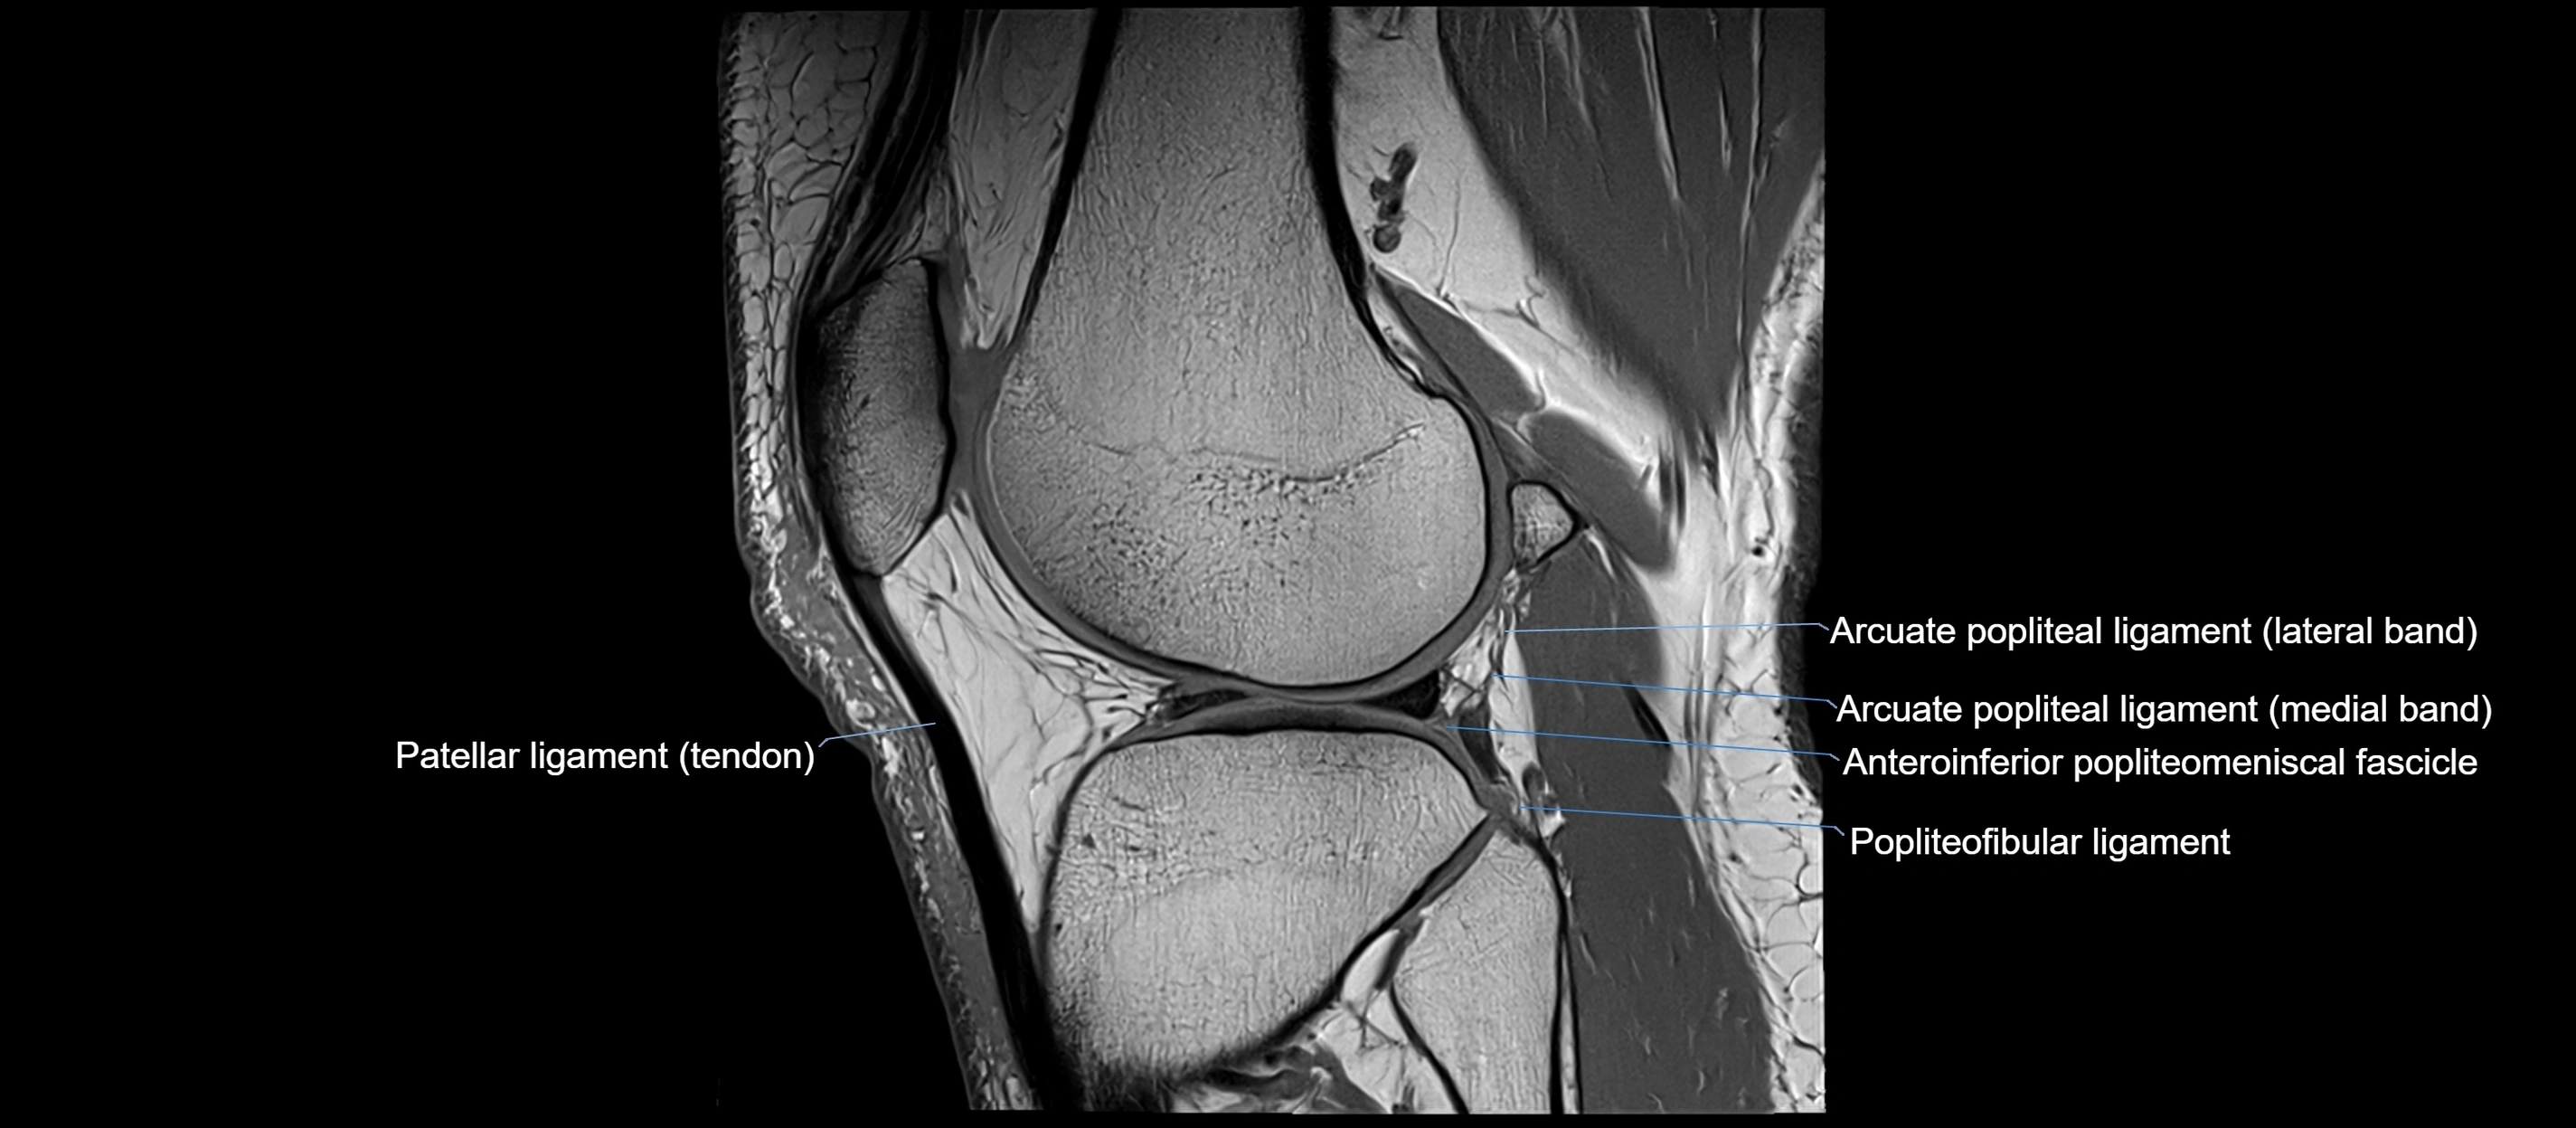

MRI images

image